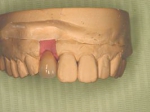

インセラム(オールセラミック)症例①

治療前治療前インセラム(オールセラミック)冠による修復。 主訴は前歯が汚い 金属を使わないオールセラミックでの治療を勧めた。 術前 治療後治療後術後